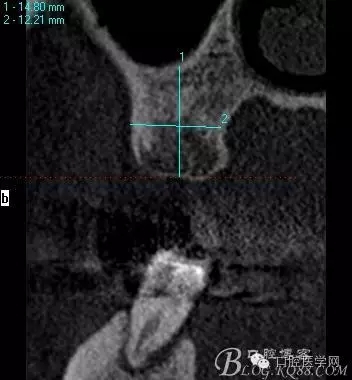

植入當然毫無難度可言,只是想術后的方向更加賞心悅目而已,14稍微有點難度,記住 上頜牙顎側(cè)骨板肯定比頰側(cè)硬多了。 所以(特別是柱行種植體柱行鉆)永遠要記住上頜牙備洞過程是會往頰側(cè)慢慢偏出去的 。(根型植體菱形鉆相對這個問題好控制點)所以我們第一鉆定位要比預計的中心點更加靠顎側(cè)多點 ,到底多多少,這個很難把握,感覺吧 。 上圖我畫了小圈的地方,是種植體離頰側(cè)和近中骨壁的距離空腔 (這個情況可以考慮植骨或者不植骨 我選擇了自體骨)。

頰顎向的方向也很理想 箭頭所示 空間填滿了自體骨